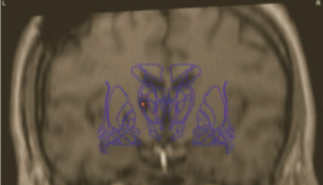

Coordinates for Voa were, according to Guiot scheme,27 0.5mm posterior to the mid-commissure point (MCP) in order to reach the posterior part of Voa and anterior part of Vop, 10mm lateral and at the level of the anterior commissure-posterior commissure (AC-PC) plane (Figure 3). Only indirect visualization was possible as conventional MRI sequences cannot delineate different thalamic nuclei.

Figure 3 Guiot Scheme, 10mm from midline AC-PC showing the Voa, Vop and Vim.

The planned electrode position was at the base of the Voa nucleus close to the Voa/Vop border (Figure 4). After carefully incising the dura at the marked point of entry a monopolar lesion making electrode (model 1017043 from Elekta, Stockholm, Sweden) was used to create a track for passage of the permanent lead. Impedance was monitored continuously to differentiate white or grey matter. Once the target was reached, macro stimulation was performed using the Leksell Neuro Generator up to supramaximal threshold of amplitude. Intraoperatively lateral fluoroscopy was used to verify the lead path and location. The actual position of the electrode was evaluated postoperatively by CT scan in stereotactic conditions and audited in the Leksell Surgiplan software (Version 10.1, Elekta, Stockholm, Sweden) (Figure 5). The difference between the planned and actual stereotactic target coordinates was up to a maximum of 0.5mm in lateral, anterior-posterior and vertical axis. The implantable neurostimulator (INS) Activa PC was implanted thereafter.

Figure 4 Left The horizontal plate from the atlas of Schaltenbrand & Wahren28 with Hassler’s29 nuclear outlines at 2mm above AC–PC plane, showing the position of the planned electrode.

Right: Same plate as at left with superimposed color-coded subcortical afferent territories extrapolated from comparable horizontal level of the monkey 24 thalamus from the atlas by Ilinsky et al.30 Somatosensory territory is shown in green, cerebellar territory in yellow, pallidal territory in navy blue, and nigral territory in burgundy. All abbreviations are as in the atlas by Schaltenbrand and Wahren.

Figure 5 The correct position of the electrode was evaluated postoperatively by CT scan in stereotactic conditions and the Surgiplan software.